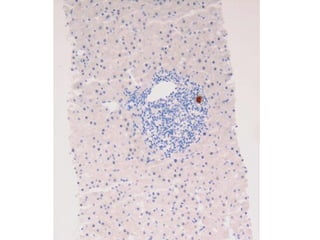

BS09-15303  Clinical history: 56 yo, female. elevated transaminase and anti-mitochondrial antibody.

BS09-15303  Dx: Primary biliary cirrhosis, Scheuer stage 1/4 (Diagnostic biopsy).

BS09-15303 Clinicalhistory: 56 yo, female. elevated transaminase and anti-mitochondrial antibody.

BS09-15303 Dx:Primary biliary cirrhosis, Scheuer stage 1/4 (Diagnostic biopsy).